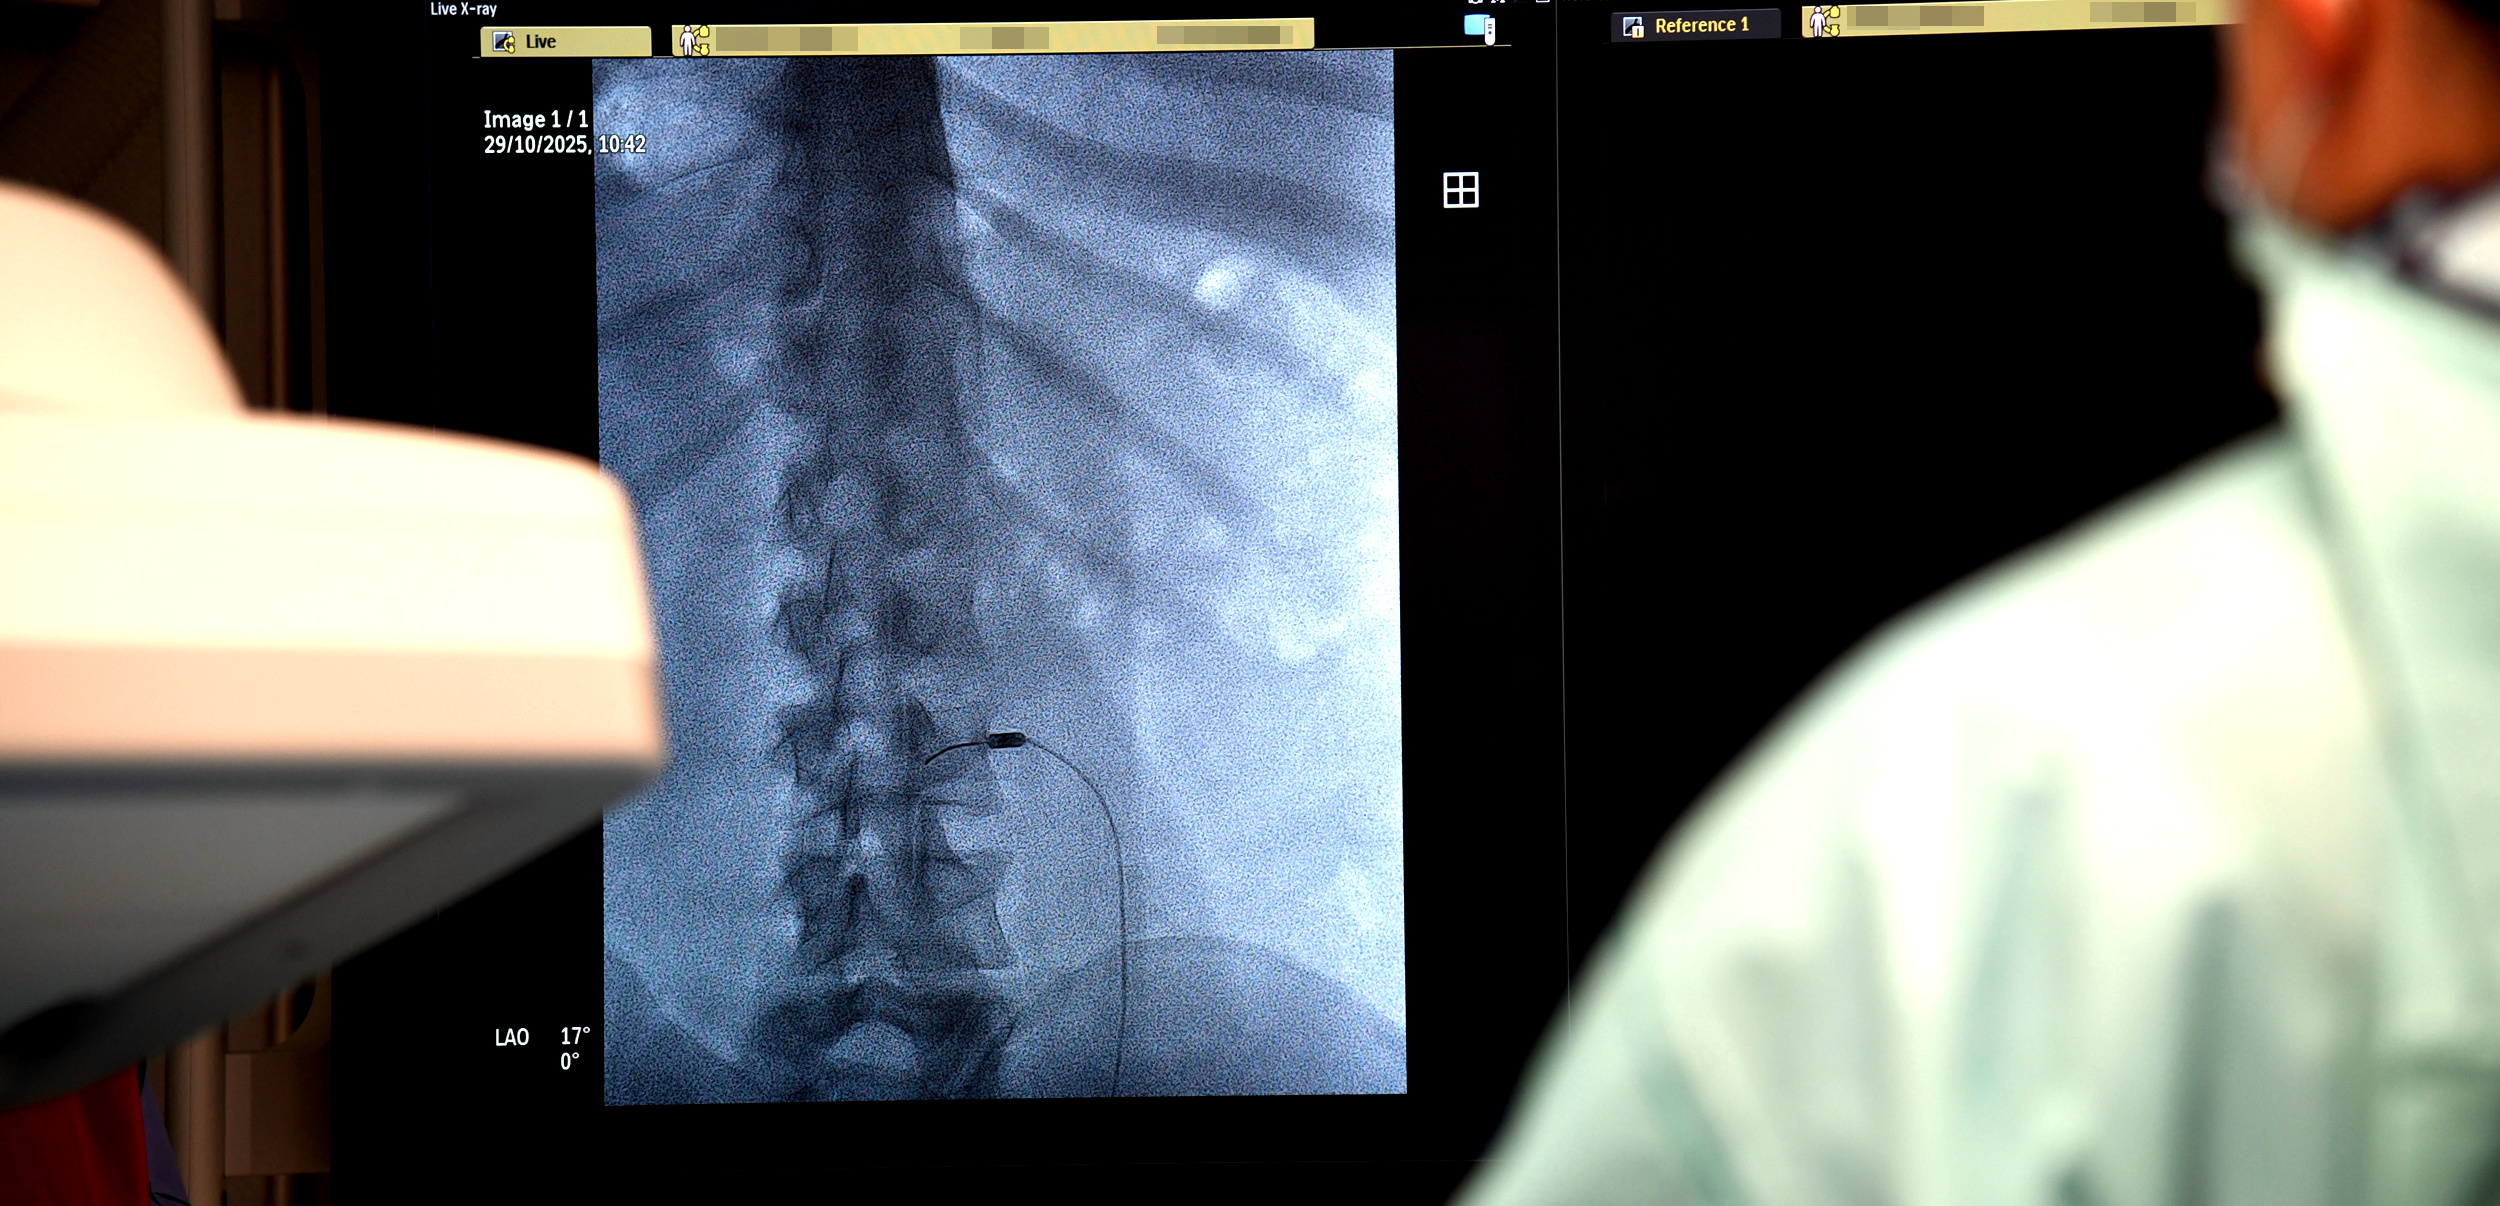

– Na przykład mamy pacjenta z bólem tak zwanym rzekomokorzeniowym. Nie ma dyskopatii, natomiast bardzo go bolą plecy. Z czego może wynikać ten ból? Z przeciążenia stawów międzykręgowych. Co możemy wtedy zrobić? Zniszczyć unerwienie tych stawów. Robimy to, wbijając igłę pod kontrolą prześwietlenia rentgenowskiego, bo jest to metoda wymagająca precyzji. Do igły wprowadzamy emiter prądów wysokiej częstotliwości i nagrzewamy tkanki do temperatury – w tym konkretnym przypadku – 85 stopni Celsjusza. Nagrzewamy miejscowo tylko tę strukturę, która nas interesuje, bo pole rażenia tej elektrody jest niewielkie – mówi Rafał Muchowski, neurochirurg z Oddziału Neurochirurgii Wojewódzkiego Szpitala Specjalistycznego w Słupsku.

Słupscy lekarze rozpoczęli wykonywanie termolezji od kręgosłupa i zamierzają swoje pole działania stopniowo rozszerzać. Obecnie przygotowują się do przeprowadzania termolezji zwoju Gassera, który jest najskuteczniejszą metodą leczenie bólu. To struktura, z której wychodzą wszystkie trzy gałęzie nerwu trójdzielnego i która bardzo często jest źródłem patologii dotyczących tego nerwu, czyli zespołów bólowych. Zabieg ten polega na wprowadzeniu igły przez usta do podstawy czaszki, do otworu walnego, gdzie mieści się zwój Gassera.

Wysoki poziom wykonywania termolezji w słupskim szpitalu jest możliwy dzięki używanemu sprzętowi wysokiej klasy, np. nowoczesnemu angiografowi zakupionemu przez szpital na początku 2025 roku.